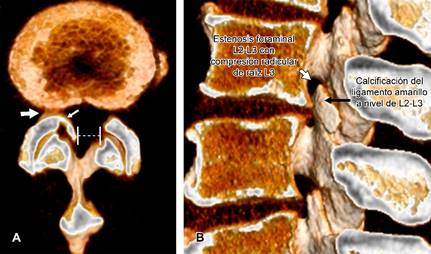

Masculino de 58 años, estibador de pieles (con peso de 40 kg) en los últimos 30 años (cargando los rollos de piel sobre hombro derecho), acude a rehabilitación derivado por medicina general debido a: dolor lumbar de cinco años de evolución con calificación 5/10 en escala visual analógica (EVA), con exacerbaciones dos a tres veces/año que mejoran con reposo de 24 horas y analgésico. La última crisis de dolor lumbar con calificación 9/10 en EVA inició un mes atrás, agregándose irradiación a cara anterior de muslo derecho, correspondiendo a dermatoma L3 que se exacerba con la ambulación y extensión de columna que mejora en decúbito lateral derecho y con la flexión de extremidades pélvicas. La tomografía de columna lumbar mostró: estenosis del canal lumbar y estenosis foraminal L2-L3 derecha, condicionada por artrosis facetaria y calcificación del ligamento amarillo ipsilateral (Figura 1). El paciente fue derivado a neurocirugía para valoración quirúrgica. La estenosis espinal degenerativa del canal lumbar es el estrechamiento del canal vertebral, del receso lateral o de los agujeros de conjunción; secundario a hipertrofia degenerativa y progresiva de cualquiera de las estructuras óseas, cartilaginosas o ligamentosas que culmina en una compresión neurológica.

Figura 1: Imágenes de tomografía computarizada en reconstrucción 3D. A) En corte axial se muestra artrosis facetaria (flecha blanca grande) y calcificación del ligamento amarillo (flecha blanca), que origina estrechamiento del receso lateral derecho en L2-L3 y canal estrecho en sentido transversal (línea punteada). B) En corte sagital se observa el estrechamiento a nivel de L2-L3 por calcificación del ligamento amarillo y artrosis facetaria.